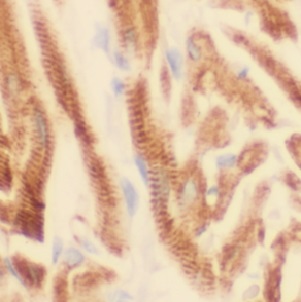

| 验证图片 | Immunohistochemistry of paraffin-embedded human heart tissue slide using FNab09318(USP21 Antibody) at dilution of 1:50 RAW 264.7 cells were subjected to SDS PAGE followed by western blot with FNab09318(USP21 Antibody) at dilution of 1:600 |